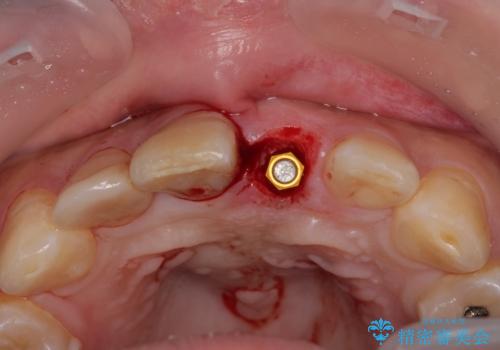

転んで折れてしまった前歯 インプラント補綴治療

- 転倒により前歯を失ったところにインプラント治療を受けたいとのことで来院された患者様です。

転倒を機に矯正治療を行ったようで、歯列が整い、インプラントのスペースができたとのことで受診をされました。

骨量は十分にあったため、インプラント埋入後速やかに仮歯を装着して、歯肉治癒後にオールセラミッククラウンによる補綴治療を行うこととしました。